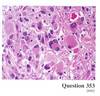

The biopsy of a 76YOM was conducted. What is the likely cause of these changes?

c) Trauma

Axonal Spheroids in Diffuse Axonal Injury (“Shear Injury”)